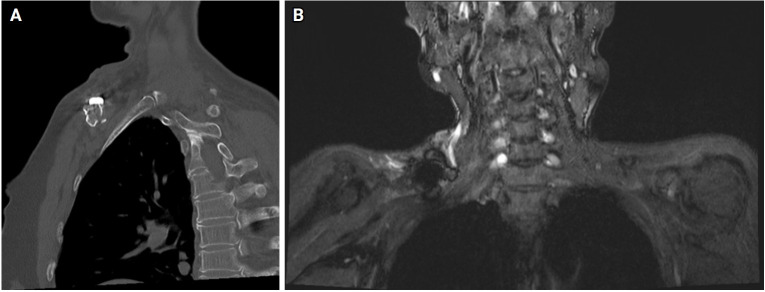

Brachial plexus paralysis is a rare but serious complication following clavicle fractures that is often linked to neurovascular compression, with an incidence of 0.5% to 9.0%. This report presents a case of brachial plexus paralysis in a 61-year-old woman after surgical fixation of a deformed mid-clavicle fracture with a metal plate. Revision surgery was performed to address the paralysis, involving removal of the metal plate, arcuate osteoplasty to create a smooth arch beneath the clavicle, and re-fixation of the plate with adjusted superior angularity. We used this approach to relieve neurovascular compression and restore thoracic outlet space. Over a period of 1 year, significant recovery and successful fracture union were achieved. This case demonstrates that managing brachial plexus paralysis with revision surgery and osteoplasty can effectively restore both neurological function and bone healing.